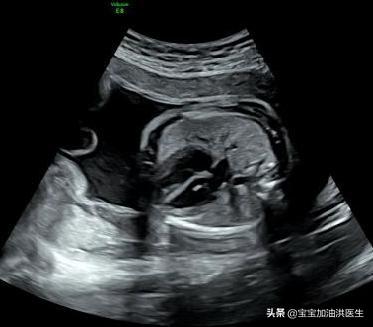

胎儿心室强光点,强光斑 , 医生在超声报告中可能会描述为心室内强回声光斑或心内灶性强回声 。 多数只有一处 , 也可多发 , 心脏的左室最多见 。 产生可能与乳头肌腱索炎症、增厚、钙化有关 , 本身无碍健康和心脏功能 , 属于一种影像上的“不同” 。

胎儿心室内强光斑是一个声像图表现 , 而不能说是一种心脏畸形;大概会有2-3%左右的胎儿检查时可能会发现这个情况存在 。

通常说胎儿出现畸形 , 还是指胎儿结构上出现了不同 , 比如哪里多了一个囊 , 或者腹腔多了一个包块 , 肺上多了一些异常情况改变 , 这类所谓胎儿器官结构的“不同” , 而这个心脏强光斑表现 , 并不是指胎儿心脏上多了或少了什么东西 , 这是局部一些超声表现的不同而已 。